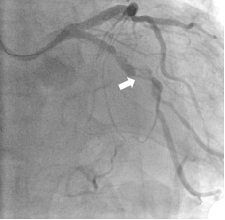

A balloon catheter was selected for pre-dilation, while it turned out that the balloon catheter could not go any further than the location shown in Fig. 4.

The TruePhysio® pressure microcatheter showed a higher crossability than the balloon catheter, which is specifically engineered for crossing the most difficult lesions and tracking anatomy.